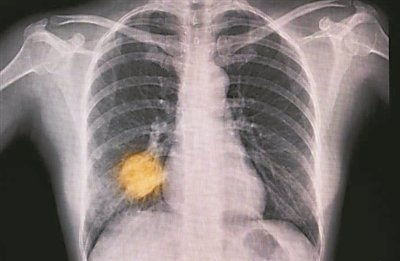

另一项进行中的试验正在追踪英国6家医院的15万名患者,测试AI能否根据胸部X光片作出肺癌早期诊断,发现哪些患者需要当天接受计算机断层扫描(CT)。